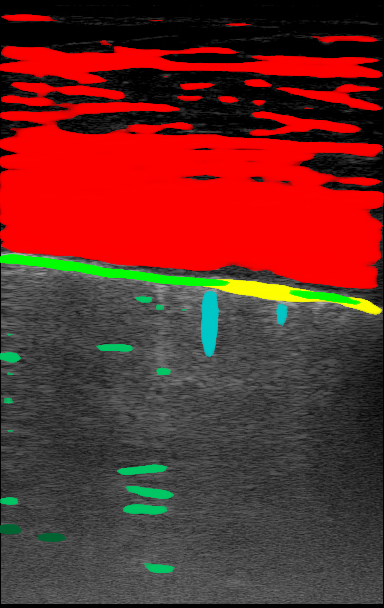

| LUS Image | Soft Label | |

|---|---|---|

Figure 1 is an example segmentation label, thresholded by confidence to show the distribution of confidences in a single example. As the confidence threshold increases, the resulting segmentation labels get more refined. However, there may be a loss of features in the labels once the thresholds get sufficiently higher than the expert’s confidence in that feature’s appearance. For example, vertical lines disappear once the threshold becomes 40% in Figure 1. By thresholding the confidence labels this way and conducting further analysis with downstream tasks, we can gain a sense of how prominent these LUS features need to be for them to be clinically relevant.